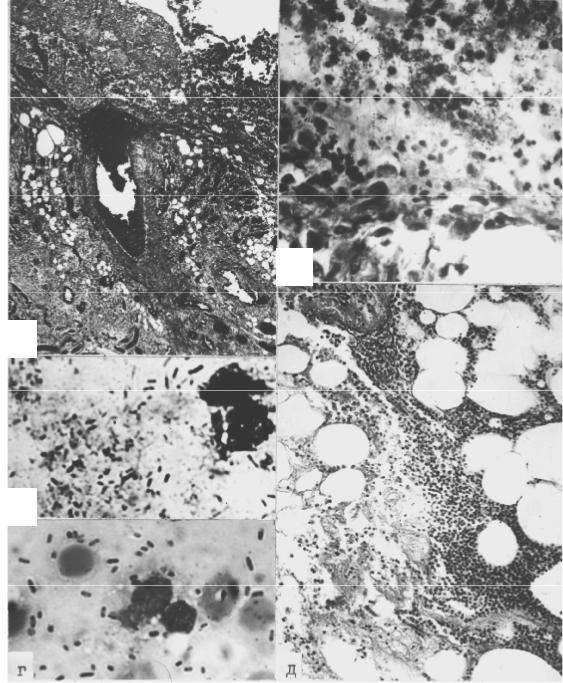

Так, золотистый стафилококк вызывает преимущественно гнойно- некротический тип тканевых изменений с образованием вокруг скоплений мик- робов зоны некроза, распространяющейся на клеточные элементы воспалитель- ного инфильтрата (рис. 24, а, б, в). Отмечается наклонность к переходу инфек- ционно-воспалительного процесса на сосуды с развитием гнойного тромбова-

скулита и к его распространению вдоль соединительнотканных фасциальных структур (рис 24, г).

а

б

в

г

Рис. 24. Стафилококковая гнойная раневая инфекция (окраска азуром II и эозином а, б, по Граму в, по Граму-Вейгерту г): а очаг инфекции Staphylococcus aureus в ране с диапедезными кровоизлияниями и распростра- нением гнойно-деструктивного процесса в глубину тканей (× 75); б некроз

лейкоцитов воспалительного инфильтрата вблизи скоплений стафилококков (× 300); в скопления стафилококков среди лейкоцитов в мазке-отпечатке той же раны (× 1000); г распространение инфекционно-воспалительного процесса по соединительнотканным прослойкам вдоль сосудов в глубину тка- ней (× 75)